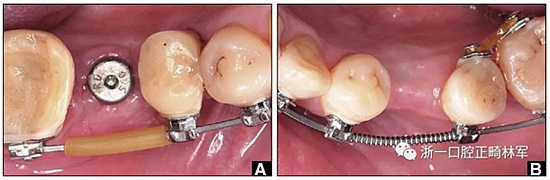

圖14. A,用固定裝置右側(cè)保持下頜第一磨牙的間隙,并在弓絲上放置塑料護(hù)套以減少軟組織刺激; B,弓絲上的推簧維持通過(guò)正畸產(chǎn)生種植位置的間隙。

圖15.A,去除固定裝置一個(gè)月后,下頜左側(cè)第二前磨牙復(fù)發(fā),移動(dòng)到種植體愈合的部位; B,B-0表示開(kāi)始再治療,通過(guò)鏈圈和推簧的矯正復(fù)發(fā); C,B-9是治療結(jié)束后3個(gè)月回訪(fǎng)時(shí)下頜弓的咬合面觀(guān),這是再治療階段的9個(gè)月。下頜左側(cè)第二前磨牙和第三磨牙的頰面粘合一個(gè)固定保持器,以防止復(fù)發(fā)。